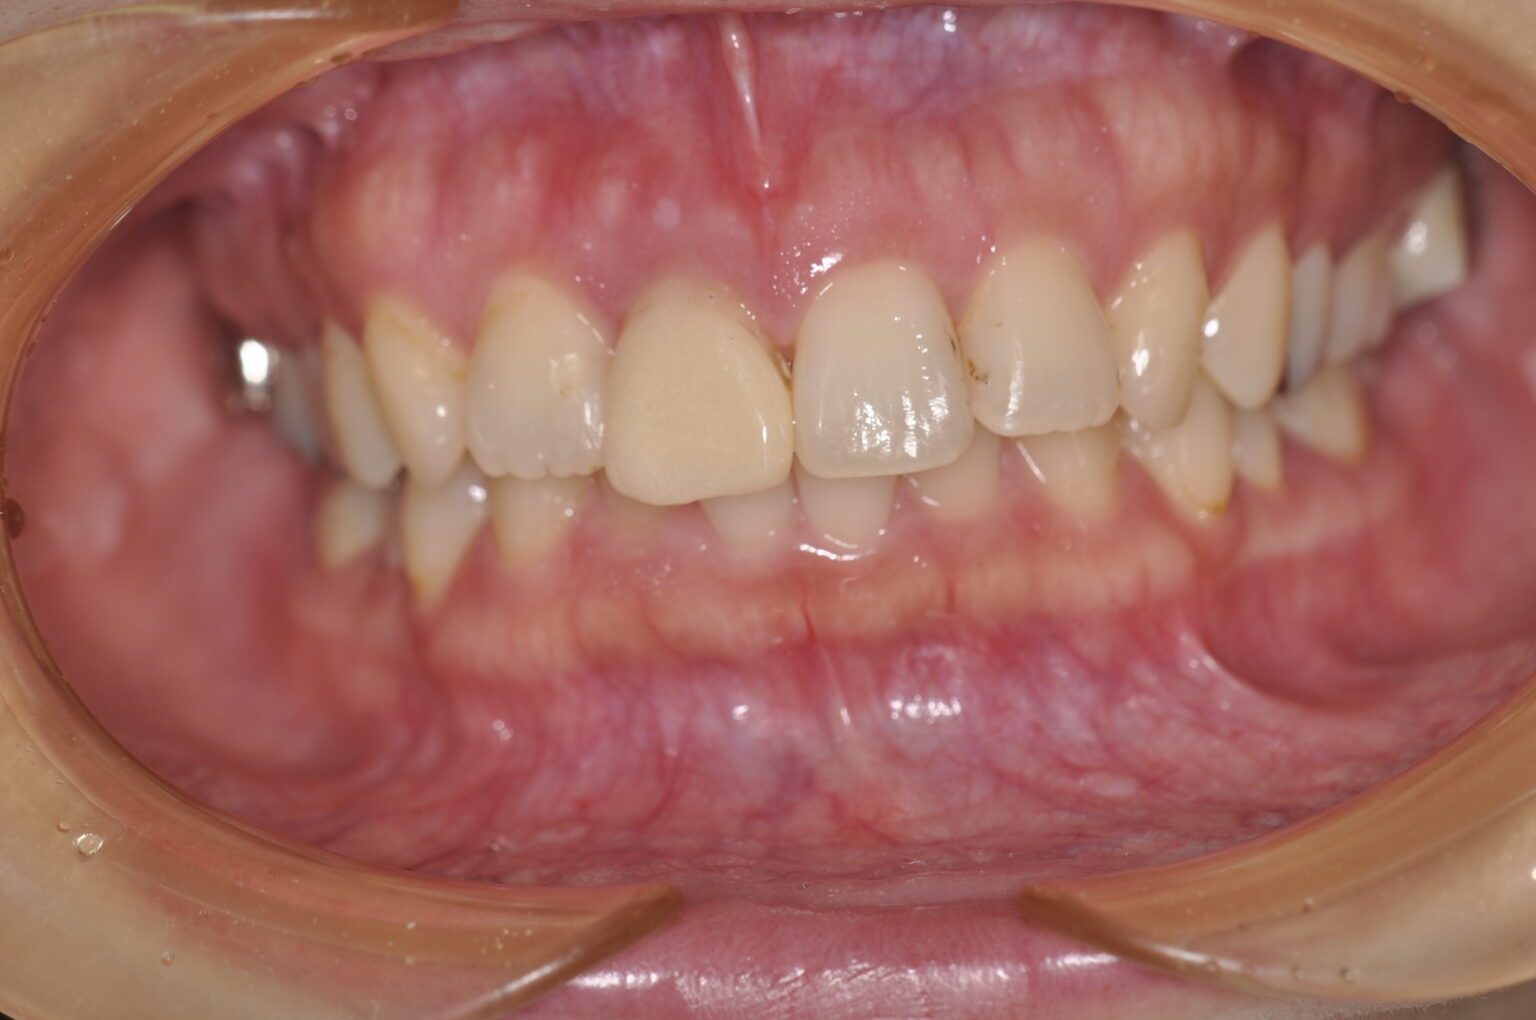

症例写真

歯周外科後に保定